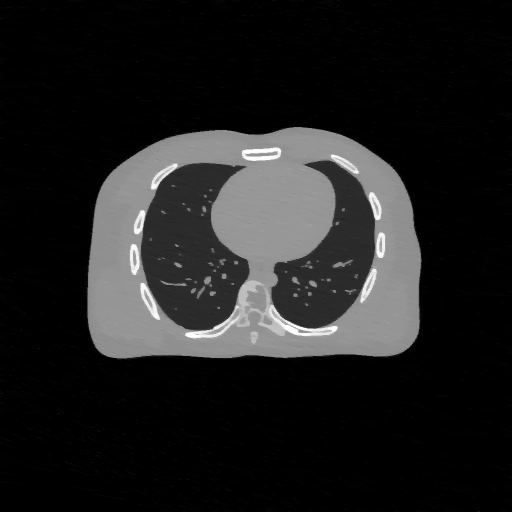

(a) Ground truth

Refer to caption

(b) PDFP, PSNR= 50.59

(c) SPDFP, PSNR= 40.27

(d) SVRG-PDFP, PSNR= 51.79

(e) OPG-ADMM, PSNR= 41.24

(f) SVRG-ADMM, PSNR= 51.75

Figure 8: Average of one slice of 3D image reconstruction of different method over 10 repetitions.

FIG. 6 give the results of PSNR of the images over time on two devices and FIG. 7 show the computation time for different algorithms to achieve a given PSNR level (if achievable). It can be seen that the stochastic algorithms are generally quicker than deterministic algorithms as the problem size of this example is much larger than 2D case. The stochastic algorithms with SVRG perform better with both GPU devices in terms of both time and accuracy. Finally, a slice of the reconstructed 3D images with different algorithms are shown in FIG. 8 to further verify the image quality of the reconstructed images of different algorithms.